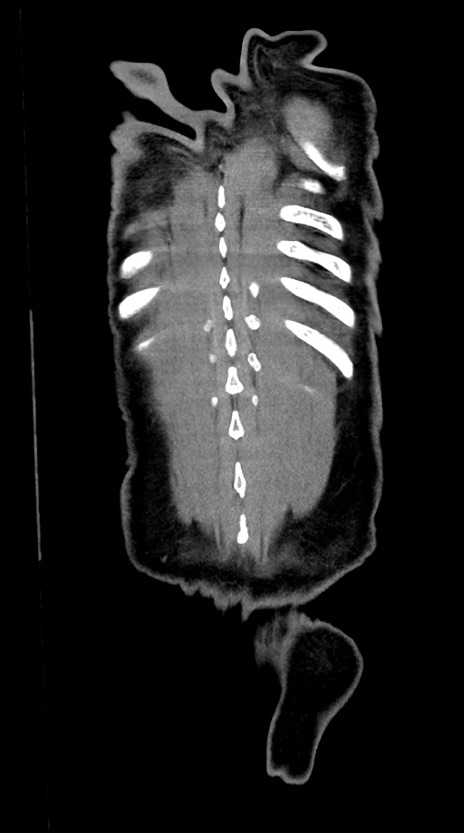

症例28(冠状断像)